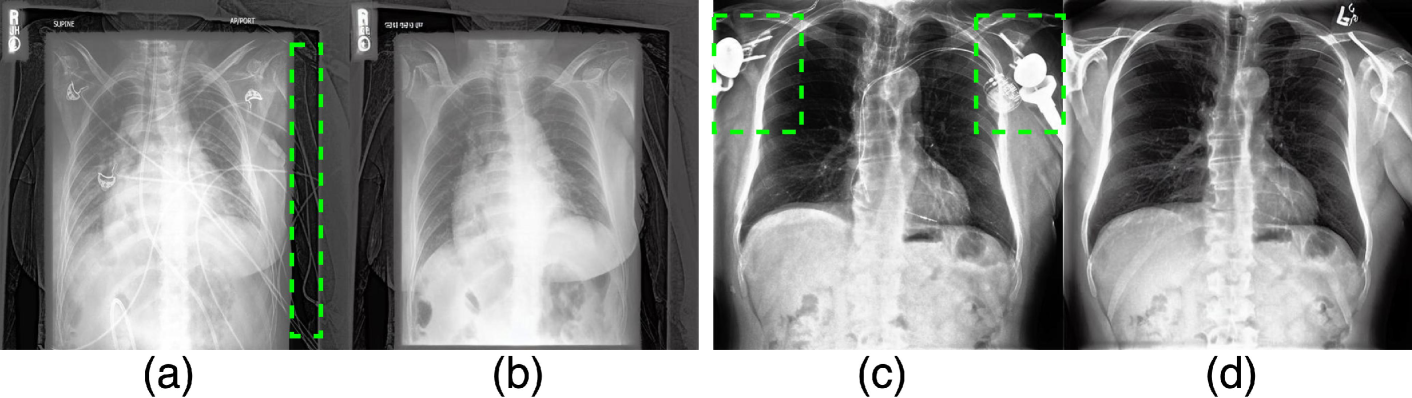

In Fig. 3, we show how, by using language guidance, we can remove complex medical devices from the given image without altering the pathology of the disease. We also compare our framework to a baseline method, GANterfactual [Mertes et al.(2022)Mertes, Huber, Weitz, Heimerl, and André], a classifier-guided CF generator. This method relies on the gradient from a pre-trained classifier for guidance and fails to remove devices from the image. Next, we evaluate our method’s ability to effectively differentiate between diseases during CF image generation. Specifically, Fig. 4 demonstrates PRISM’s performance in generating CFs for two diseases: Pleural Effusion and Cardiomegaly.

Refer to caption

Figure 4: Sample pairs of original and edited images showcasing accurate, precise and high-resolution generated CFs for disease pathology explainability. The original (T𝑇Titalic_T) and edited text prompts (Tsuperscript𝑇T^{\prime}italic_T start_POSTSUPERSCRIPT ′ end_POSTSUPERSCRIPT) are - Row 1: T𝑇Titalic_T - chest x-ray of the patient with severe pleural effusion, Tsuperscript𝑇T^{\prime}italic_T start_POSTSUPERSCRIPT ′ end_POSTSUPERSCRIPT - chest x-ray of the patient with no finding; Row 2: T𝑇Titalic_T - chest x-ray of the patient with severe cardiomegaly, Tsuperscript𝑇T^{\prime}italic_T start_POSTSUPERSCRIPT ′ end_POSTSUPERSCRIPT - chest x-ray of the patient with no finding.

The difference maps in Fig. 4 demonstrate that our approach can identify and remove the target disease while preserving the anatomical features of the subject, as well as the devices and other artifacts outside the regions of the expected changes. In Appendix B, we provide additional qualitative comparisons between PRISM and state-of-the-art (SOTA) text-guided image editing methods, including Imagic [Kawar et al.(2023)Kawar, Zada, Lang, Tov, Chang, Dekel, Mosseri, and Irani], Null-text Inversion [Mokady et al.(2023)Mokady, Hertz, Aberman, Pritch, and Cohen-Or], and RadEdit [Pérez-García et al.(2025)Pérez-García, Bond-Taylor, Sanchez, van Breugel, Castro, Sharma, Salvatelli, Wetscherek, Richardson, Lungren, et al.]. The results demonstrate PRISM’s ability to generate precise CF images that remain consistent with the original factual image, outperforming other methods.